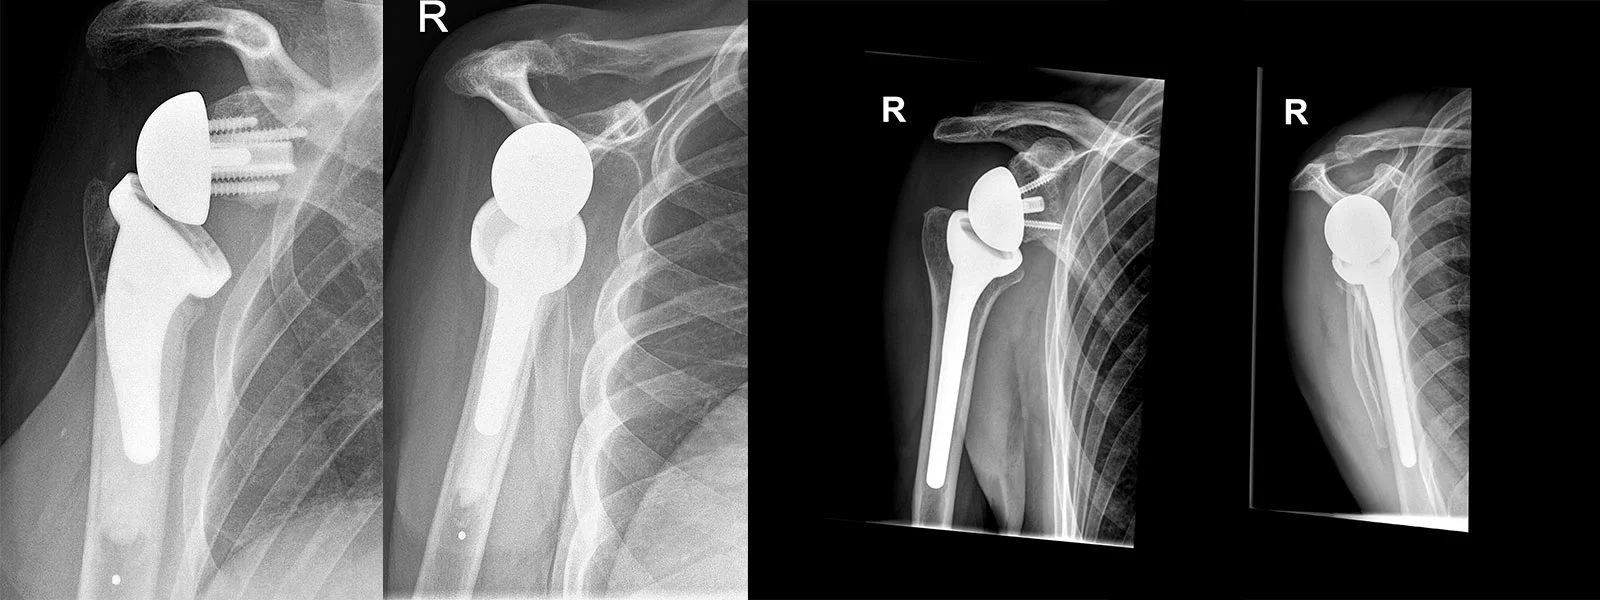

Die umgekehrte (inverse Schulterprothese)

Ist die Rotatorenmanschette der Schulter gerissen, kommt nur noch die sog. inverse Schulter-Totalprothese in Betracht. Hier wird ein Ingenieurs-Trick angewendet. Der Kopf der wird an der Schulter befestigt und die Pfanne am Oberarm. Dadurch wird das Drehzentrum nach innen und unten verlagert, womit der Deltamuskel angespannt und zum primären Motor der Schulter wird. Die Funktion dieser Prothesen ist sehr gut. Eine Lebensdauer nach Implantation kann 10-15 Jahre betragen.

Gelegentlich sind alle Sehnen der Schulter rupturiert, sodass der Patient eine schwere Funktionsstörung hat. Hier muss man die inverse Schulter-Totalprothese mit einem Latissimus dorsi-Transfer kombinieren.